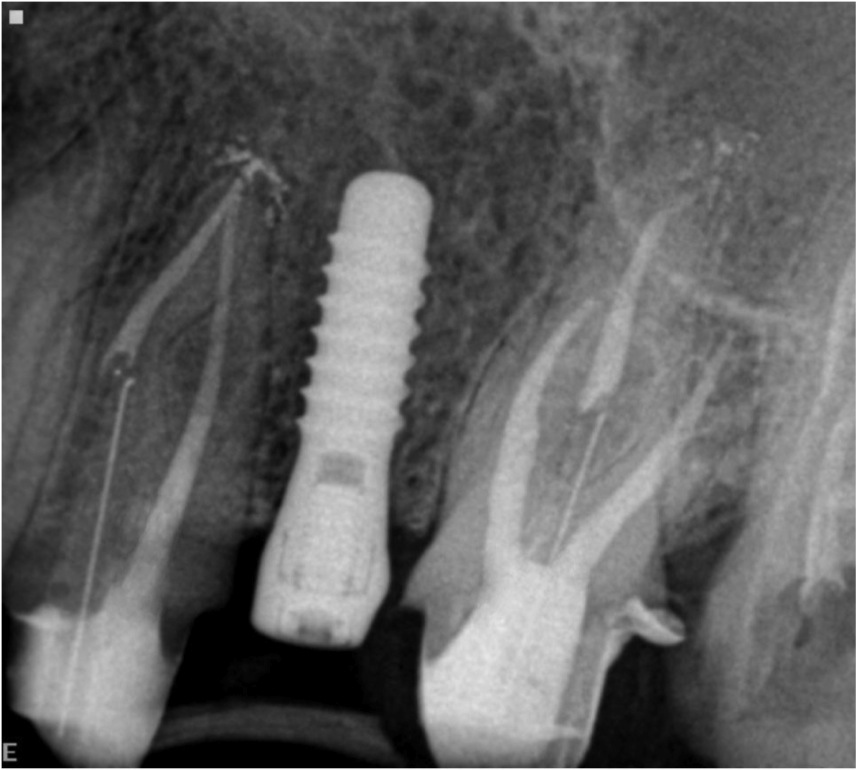

Rx final do caso